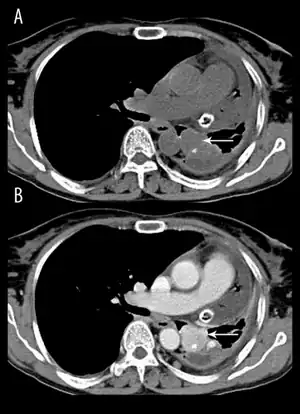

Diagnosis may be difficult in patients in whom paraneoplastic antibodies cannot be detected. In the absence of these antibodies, other tests that may be helpful include MRI, PET, lumbar puncture and electrophysiology.[6]